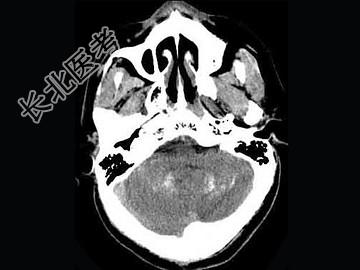

- 单项选择题男,52岁, 无明显不适,CT检查, 最可能的诊断为 ( )

A、脑血管畸形

B、结节性硬化

C、甲状旁腺功能低下

D、脑颜面血管瘤病

E、转移瘤